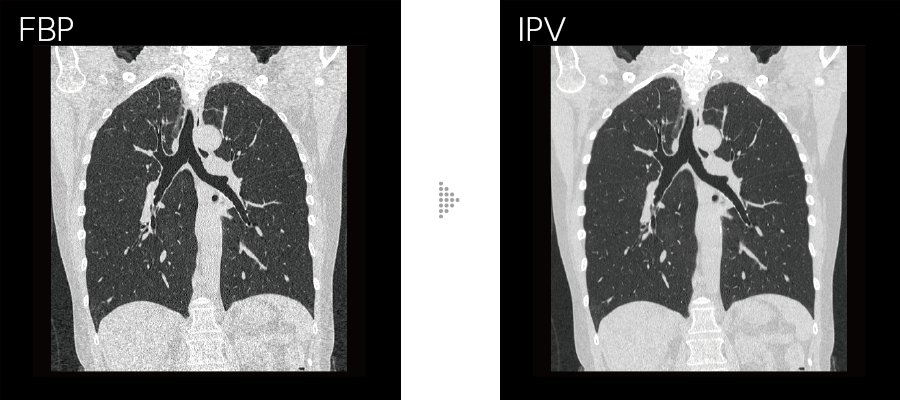

胸部領域全体で画像のブレを抑える

従来の胸部CT検査*1は、心拍動の影響や被検者の体動などにより画像のブレが発生し、診断が難しいケースがありました。Body StillShotは、収集したRawDataから被写体の動く方向と量を4次元的に算出し、動きによるブレの少ない画像を提供します。AI技術を活用して開発した画像再構成技術IPVとの併用も可能で、さらなる高画質化に寄与します。

IPVはAI技術*4を活用して開発した画像再構成です。充分な反復処理により得られる画像を教師データとして処理を高速化。富士フイルムが開発したVisual Modelに基づき、RawDataを起点とした画像再構成処理により、NPS(Noise Power Spectrum)をFBP(Filtered Back Projection)に近づけ、高いノイズ低減率においても、画像の質感変化を抑えます。画像ノイズを最大90%*5低減し、被ばく量は最大83%*6低減。低コントラスト検出能を最大2倍*6に改善します。

高周波から低周波まで均等な割合でテクスチャを調整しながら視認性に影響を与えるノイズ周波数特性をFBPに近づけました。